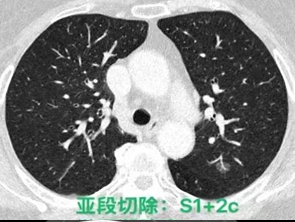

常规腔镜方面,以胸部肿瘤外科为主,开展肺叶、肺段、复合肺段/亚段切除、解剖性肺切除、袖状切除等手术,包括单孔到多孔等各种入路。在北京市较早开展微创食管癌切除,积累了丰富的经验。纵隔肿瘤方面,开展包括剑突下及其他入路胸腺切除、胸腺扩大切除,无名静脉成型等。同时结合锚丝定位、术前三维重建技术和荧光腔镜技术使手术安全高效。

目前主流的胸外科微创手术业务我科已达到全覆盖。包括但不限于:胸腔镜下肺叶、肺段、亚段、联合亚段、全肺、肺袖状切除术;单孔胸腔镜微创手术,Hook-Wire定位小结节精准切除手术,微创胸腹腔镜联合食管癌切除术,剑突下纵隔肿物切除术,达芬奇机器人辅助各类手术等几乎所有的胸外科先进微创的手术方式。

各类联合亚段切除术